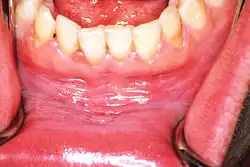

Homogeneous leukoplakia

Homogeneous leukoplakia (also termed "thick leukoplakia")[2] is usually well defined white patch of uniform, flat appearance and texture, although there may be superficial irregularities.[2][9] Homogeneous leukoplakia is usually slightly elevated compared to surrounding mucosa, and often has a fissured, wrinkled or corrugated surface texture,[2] with the texture generally consistent throughout the whole lesion. This term has no implications on the size of the lesion, which may be localized or extensive.[2] When homogeneous leukoplakia is palpated, it may feel leathery, dry, or like cracked mud.[2]